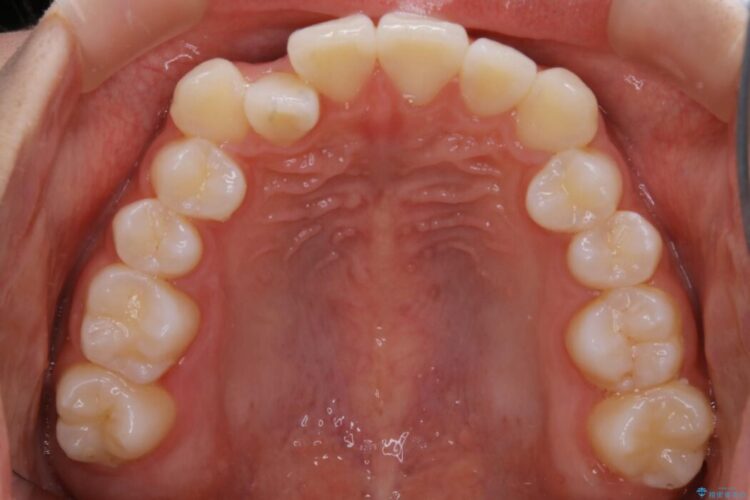

詳しく検査したところ、上顎の歯が舌側に倒れこんでしまっていることや歯列のガタガタなどにより口を閉じた時に上下の前歯の先端が接触してしまっていました。

よってまずは上顎の歯列を整えることから始め、前歯同士の衝突を改善してから、噛みこむ位置を本来あるべき後方へと調整することとしました。

今回のケースでは非抜歯での治療を行っています。